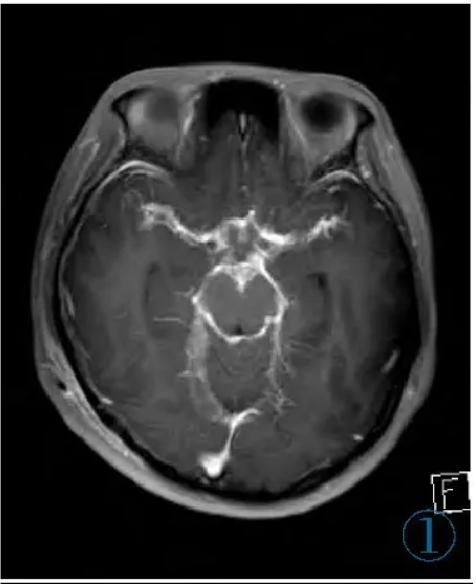

颅脑MRI示鞍上池、环池、侧裂池等区域的软脑膜呈弥漫性增厚、强化(图1),其中最大的结节凸向右侧桥脑前池,大小约11 mm×8 mm,呈宽基底与邻近脑膜相连,T1WI及T2WI呈等信号,增强扫描轻度强化,DWI未见弥散受限,PET-CT示该结节与脑膜病灶代谢轻度增高(图2~5)。脑室系统广泛扩张。左肺下叶外基底段可见数个实性小结节,边界清,直径约1~3 mm,代谢未见异常。

图1 横断位增强T1WI示鞍上池、环池、侧裂池等区域的软脑膜呈弥漫性增厚、强化。